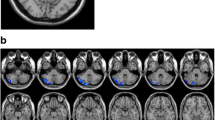

Corresponding ICA images were independently selected from the two groups according to the templates presented by GIFT. Forty-eight components were obtained, 21 of which were selected as the resting-state network: 2 components in the language network, 3 in the default mode network (DMN), 3 in the visual network, 3 in the executive network, 3 in the sensorimotor network, 2 in the salience network, 4 in the attention network, and the remaining component in the cerebellum (Fig. S1). Age, gender, and BMI were used as covariates for group comparison between patients and controls and the differences are shown in Table 2 and Fig. 1. Compared with controls, decreased FC in the right caudate within the salience network (Fig. 1A) and decreased FC in the left medial frontal gyrus within executive network (Fig. 1B) were found in narcolepsy patients, while increased FC in the bilateral middle frontal gyrus within the executive network (Fig. 1B) was also found in patients.

Sparsity values were selected in the analysis of nodal topological properties. Many brain nodes showed altered topological properties between narcolepsy patients and healthy controls. Specifically, eight overlapping nodes – the bilateral inferior frontal gyrus (IFG), right anterior cingulate gyrus (ACG), left supplementary motor area (SMA), right calcarine fissure (CAL), and bilateral basal ganglia – had the same alterations in centrality measurements (BC and DC) in patients and controls (Fig. 3 and Table 3). Meanwhile, six overlapping nodes – the left IFG, left ACG, left posterior cingulate gyrus (PCG), bilateral posterior central gyrus (PoCG), and left caudate (CAU) – had the same alterations in clustering measurements (NCC and NE) in patients and controls (Fig. 4 and Table 3).

Nodal Functional Connectivity Analysis

Among the eight overlapping nodes in centrality differences between groups, increased FC among anterior brain areas (IFG, ACG, SMA, and basal ganglia) was found in narcolepsy patients compared with healthy controls, while decreased FC between the right CAL and some anterior brain areas (left IFG, SMA, and ACG) was detected in patients compared with controls (Fig. 3 and Table S1). Among the six overlapping nodes in clustering differences between groups, decreased FC between the left ACG and left PCG as well as FC among the bilateral PoCG was found in patients compared with controls, while FC between the left IFG or left ACG and the bilateral PoCG was higher in patients than in controls. Moreover, FC between the left PCG and bilateral PoCG as well as FC between the left IFG and left CAU was also higher in patients than in controls (Fig. 4 and Table S1).

We found decreased FC in the left medial frontal gyrus within the executive network and decreased FC in the right caudate within the salience network in adult narcolepsy patients compared with healthy controls. Compared with controls, increased FC in the bilateral middle frontal gyrus within the executive network was detected in the narcolepsy patients.

Alterations of centrality demonstrated overlapping areas in the bilateral IFG, right ACG, left SMA, bilateral basal ganglia, and right CAL between patients and controls. Excitatory hypocretin innervation of visual neurons has been described in a previous study [55], so we infer that the decreased BC and DC in the right CAL may be related to the reduced excitation by hypocretin in narcolepsy. Increased BC and DC in the right ACG is consistent with a positron emission tomography study, in which hyper-metabolism in the anterior cingulate cortex was revealed in narcolepsy patients under fully awake conditions [6]. The increased BC and DC in the bilateral IFG is partially in agreement with the ICA results from the present study, in which increased FC in the bilateral middle frontal gyrus also reflected the subjective effort to maintain alertness, and methodological differences in ICA and graph theoretical analysis led to the diversity of results in ICA and centrality measurements in the bilateral frontal lobe. Partial correlation analysis showed that DC in the left putamen was negatively correlated with mean REM sleep latency among narcolepsy patients, and this indicated that increased DC in the left putamen might be associated with the pathophysiology of sleepiness in narcolepsy.

Hypo-excitability in the sensorimotor cortex due to deficient hypocretin excitatory innervation has been reported in narcolepsy by transcranial magnetic stimulation [56], which could explain the reduced NCC and NE in the bilateral PoCG in the present study. Partial correlation analysis also suggested that NE in the bilateral PoCG was negatively correlated with ESS among patients, indicating that decreased NE in the postcentral gyrus on both sides was associated with the severity of subjective sleepiness in narcolepsy. PCG is a core node in the DMN, and a disrupted DMN has been shown to be disease-specific for narcolepsy in an EEG-fMRI study [57]. Moreover, partial correlation analysis showed that NE in the PCG is positively correlated with the mean REM sleep latency, indicating that reduced NE in the PCG was also associated with the pathophysiology of sleepiness in narcolepsy. Enhanced NE and NCC in the left ACG, left IFG, and left basal ganglia was consistent with the increased BC and DC within these areas in the present study; also, the increased NE in left ACG was correlated with the severity of subjective ESS.

An increased FC between the right ACG and bilateral basal ganglia (left putamen and right pallidum) was found in narcolepsy patients compared with healthy controls. Both the ACG and basal ganglia are core components of the salience network [50, 51], and increased FC among these areas is consistent with the results of previous narcolepsy studies of the salience network [48, 53]. Increased FC between the bilateral IFG and right ACG as well as the basal ganglia implies an enhanced connection between the executive and salience networks, and this might partially explain the increased FC in the bilateral frontal lobe within the executive network in our ICA results. Both increased FC within the salience network and between the executive and salience networks indicate the subjective effort to maintain wakefulness during the MRI scan [49, 52]. Especially, FC between the left IFG and left CAU was negatively correlated with REM sleep latency in narcolepsy patients, demonstrating that increased FC between the left IFG and left CAU might be associated with the pathophysiology of sleepiness in narcolepsy. The SMA is involved in motion adjustment and coordination [58]. FC between the left SMA and right ACG was positively correlated with REM sleep latency, and the FC between the left SMA and right CAL was positively correlated with ESS in narcolepsy patients, indicating that abnormal activity in the SMA and its connections might also be associated with the abnormal sleepiness in narcolepsy. Also, decreased FC between the right CAL and left IFG as well as decreased FC between the right CAL and right ACG was found in patients compared with controls. This decreased FC might be correlated with the decreased centrality in the right CAL just as in the graph theoretical analysis results in the present study.

Decreased FC among the bilateral PoCG was in accord with the changes in topological properties in the bilateral PoCG, which is associated with hypo-excitability within these areas due to hypocretin dysfunction [56]. Decreased FC between the left PCG and left ACG demonstrated a potential dysfunctional connection between the salience network and the DMN; this has rarely been reported in previous studies. FC between the left ACG and bilateral PoCG was negatively correlated with REM sleep latency, which implied that increased FC between the left ACG and bilateral PoCG might also be associated with the pathophysiology of sleepiness in narcolepsy. Increased FC between the left PCG and bilateral PoCG might be a compensation for decreased NE/NCC within these areas in narcolepsy patients.